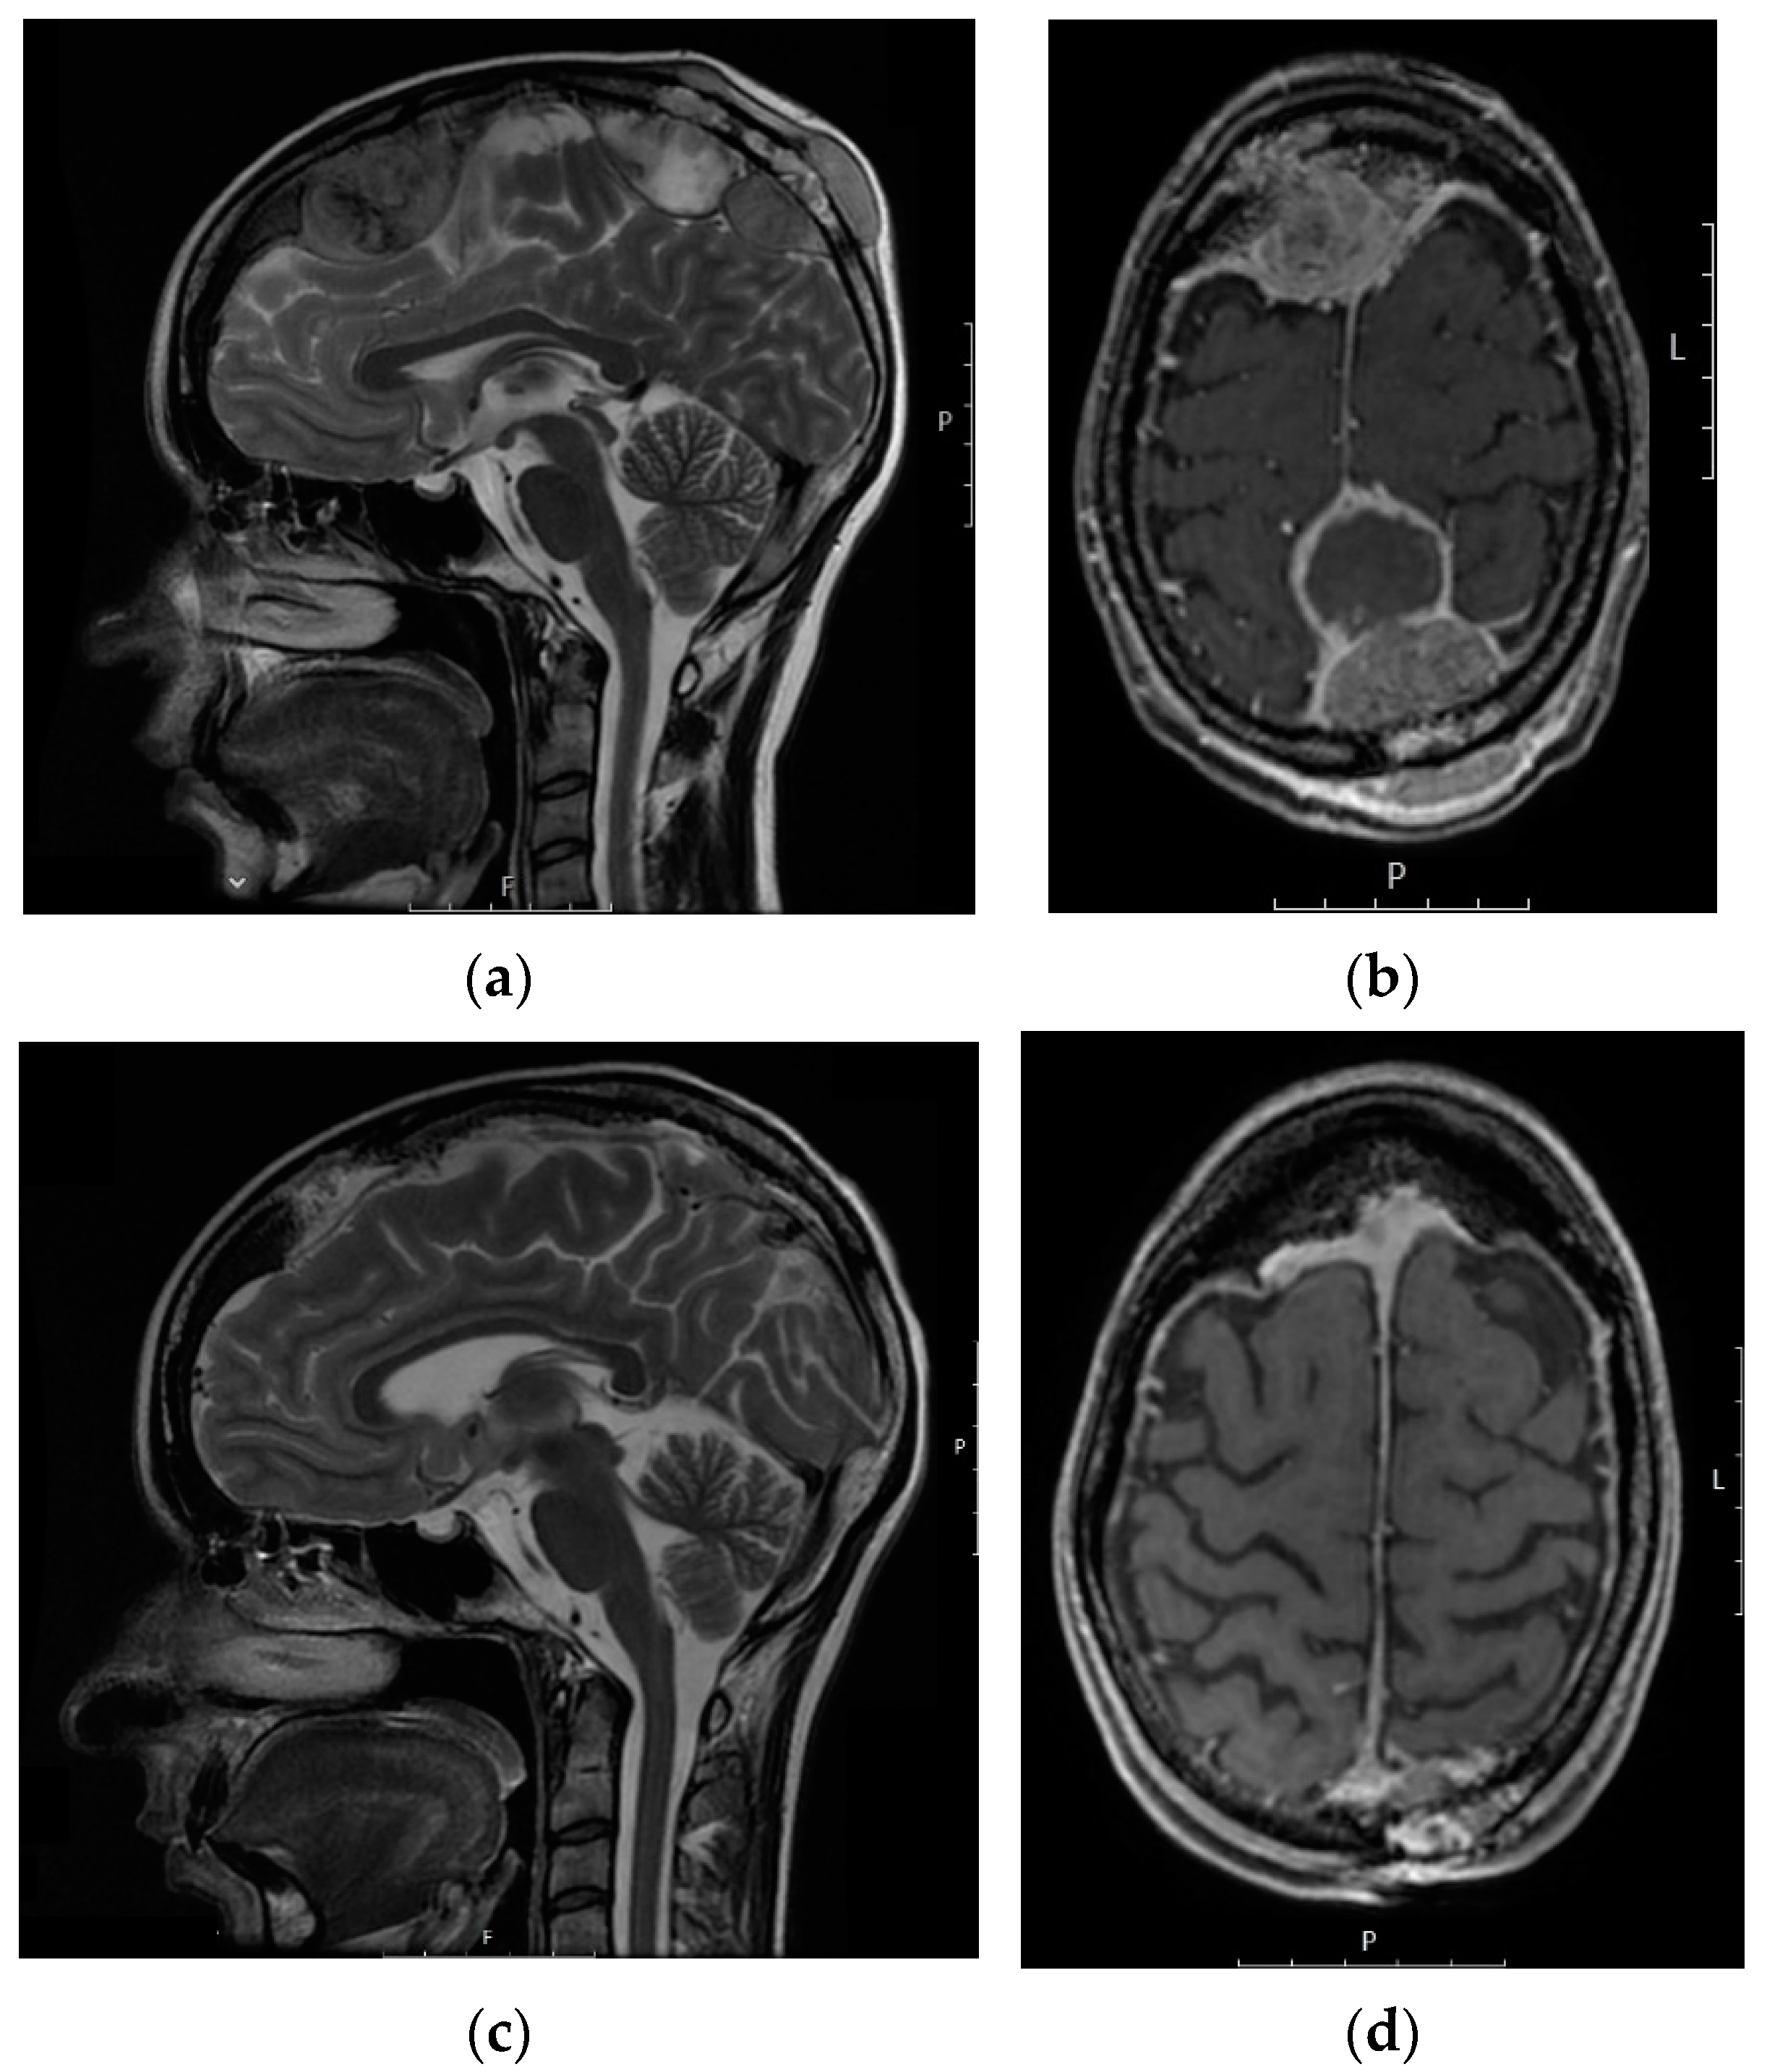

- Kokkali, S.; Andriotis, E.; Katsarou, E.; Theocharis, A.; Drizou, M.; Magou, E.; Tzovaras, A.; Ardavanis, A. Cerebral Metastasis from Osteosarcoma: “Bone” in the Brain. Radiol. Case Rep. 2020, 15, 780–783. [Google Scholar] [CrossRef]